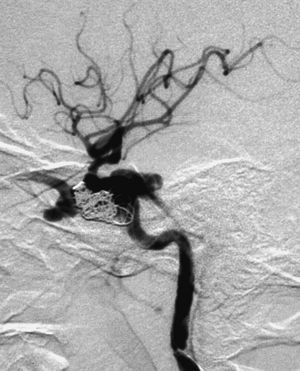

En los casos en los que el tratamiento conservador no ha sido eficaz10, cuando existen manifestaciones clínicas o angiográficas que asocian mal pronóstico, que ya hemos comentado, está indicada la terapia endovascular. La vía de abordaje puede ser arterial o venosa. Inicialmente se prefería la colocación de balones por vía arterial27-29. Con este procedimiento se conseguía cierre de la fístula con preservación de ACI casi en el 90% de los casos, sin embargo la tasa de complicaciones mayores era del 5%, consistiendo en isquemia cerebral transitoria e infartos tromboembólicos o isquémicos30. Los pseudoaneurismas post-tratamiento aparecían hasta en un 44% de los casos y se debían al hueco dejado por el desinflado del balón, pero su trascendencia clínica era escasa28,31. Hoy en día este procedimiento ha sido sustituido por otros gracias al desarrollo y empleo de nuevos materiales y/o vías de abordaje32. Se prefieren los coils en la práctica habitual (fig. 4).

Fig. 4.--A) Arteriografía cerebral con inyección de contraste desde la arteria carótida interna (ACI) en proyección lateral demuestra la existencia de una brecha o fístula directa, de alto flujo, en la porción intracavernosa en una paciente de 28 años con antecedente traumático. Asimismo se observa flujo venoso retrógrado a la vena oftálmica, que está muy dilatada. B) Cateterización selectiva de ACI y colocación de coils en el seno cavernoso por vía transarterial. C) Control arteriográfico tras la embolización transarterial con coils, con inyección de contraste en ACI, en fase arterial y proyección lateral, donde se aprecia empaquetamiento del seno cavernoso. Persiste todavía la dilatación de la vena oftálmica, que desapareció a los pocos días, con mejoría clínica completa.

En nuestro grupo de 10 pacientes con FCC directa tratada mediante embolización, en 5 procedimientos el abordaje fue por vía arterial exclusivamente, colocando como material embolígeno en 2 casos balones y en 3 coils (fig. 4). En 4 casos la mejoría de la sintomatología fue completa, mientras que en uno fue parcial. Tan sólo en un paciente se tuvo que realizar la exclusión completa de la arteria carótida ya que la ACI estaba muy deteriorada. Previamente realizamos el test de oclusión con objeto de conocer cuál sería el efecto de la exclusión carotídea.